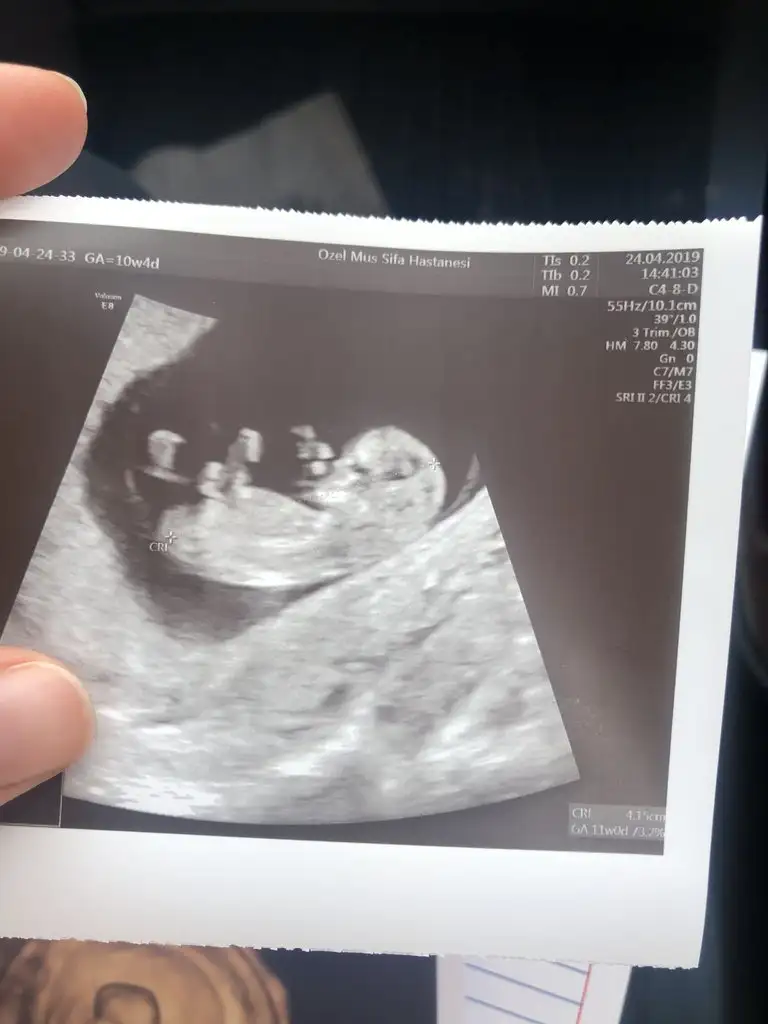

Hanımlar bizde 10+4 haftalığız sizce cinsiyeti ne olabilir doktor net bişey söylemedi

Bence henüz erken ama 12. haftasında da Genitali böyle durursa kız olabilir çıkıntı yok henüz ama 12. Hafta netleşir diye düşünüyorum